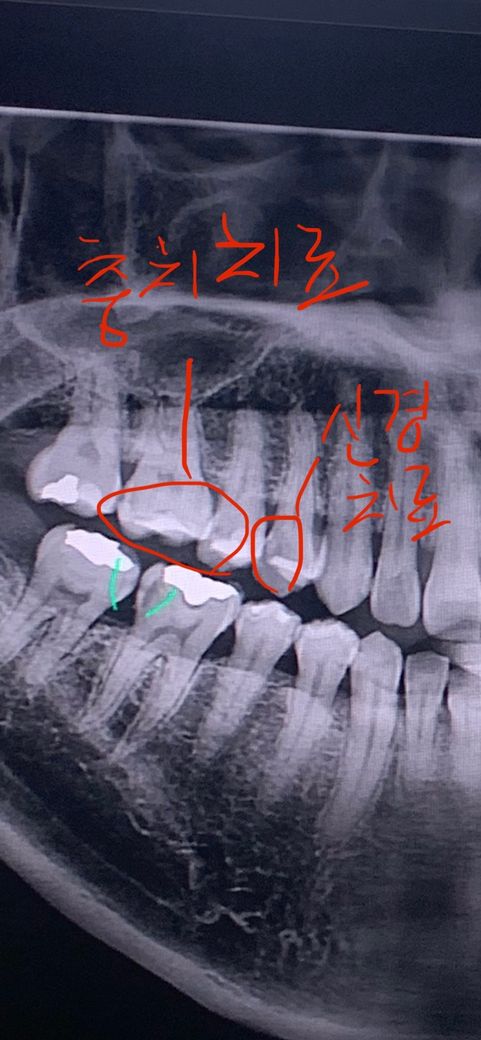

치아 엑스레이 충치 봐주시면 감사하겠습다!

현재 오른쪽 빨간색 신경치료 포스트하고 크라운 예정입니다.

신경치료 후 왼쪽 빨간색부분 충치 치료 후 세라믹 인레이를 해야한다고 합니다.

왼쪽 빨간색 동그라미 충치가 치료를 해야 할 정도인지 어느정도 인지 질문드립니다. 감사합니다.

큰 어금니는 기존 수복물 하방으로 이차충치 있어보이고, 작은어금니는 옆면으로 충치가 있네요 적절한 치료 계획입니다

작은어금니는 충치가 많이 진행된 것으로 보이며, 큰어금니는 많이는 진행 안되었지만 충치는 확인되는 상태입니다. 작은 어금니는 인접면 충치 즉 치아와 치아 사이 충치입니다.